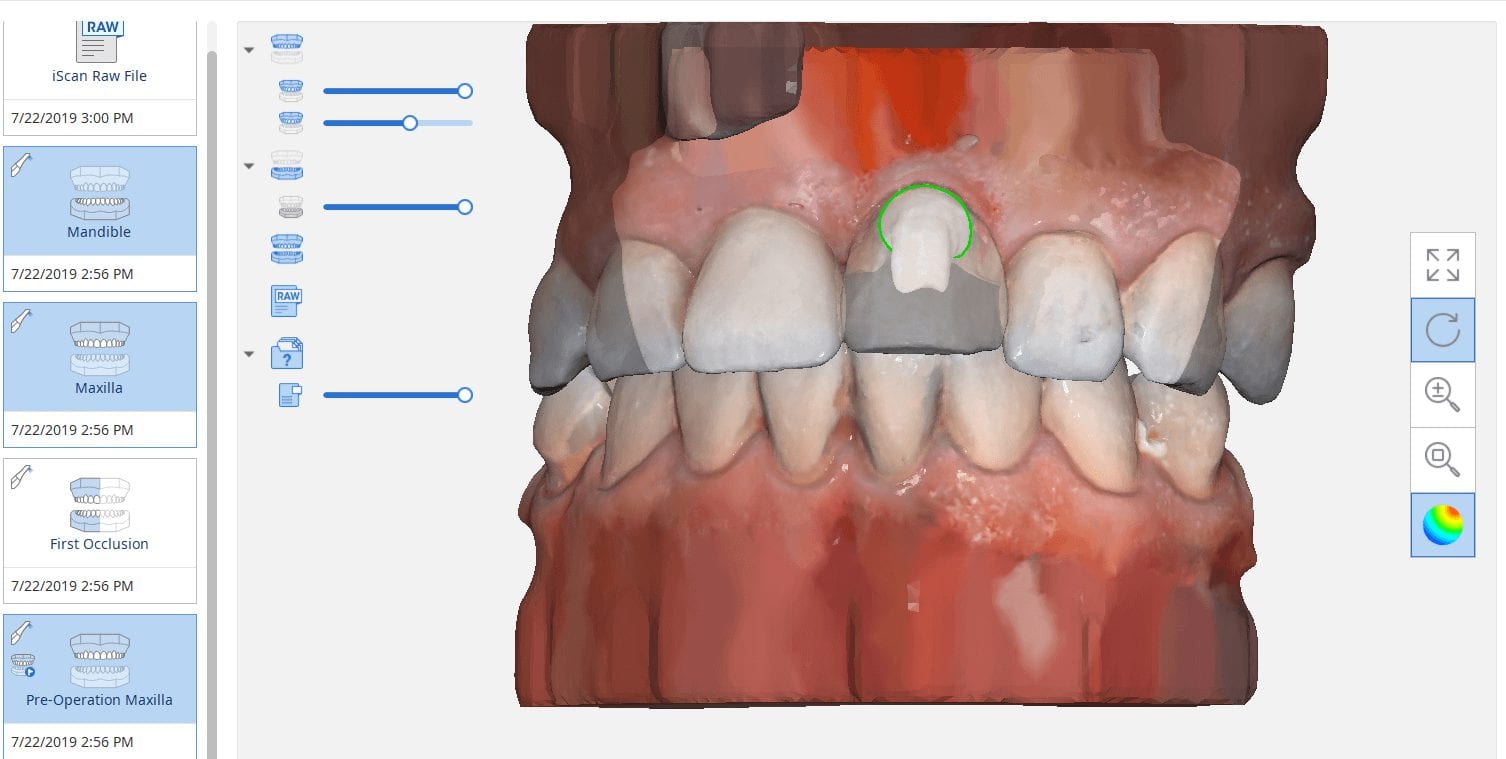

Marking Margins in Medit i500 Before Sending a Case to a Lab or CAD Software Like exocad

July 22, 2019The new Medit i500 software will feature the ability to mark margins in the imaging step before you import the case into a CAD software or send it to the […]